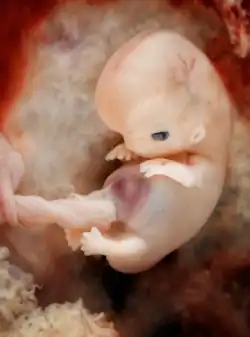

Nine-week-old human embryo from an ectopic pregnancy

Organogenesis is the development of the organs that begins during the third to eighth week, and continues until birth. Sometimes full development, as in the lungs, continues after birth. Different organs take part in the development of the many organ systems of the body.

Human embryo at 7-8 weeks from conception.